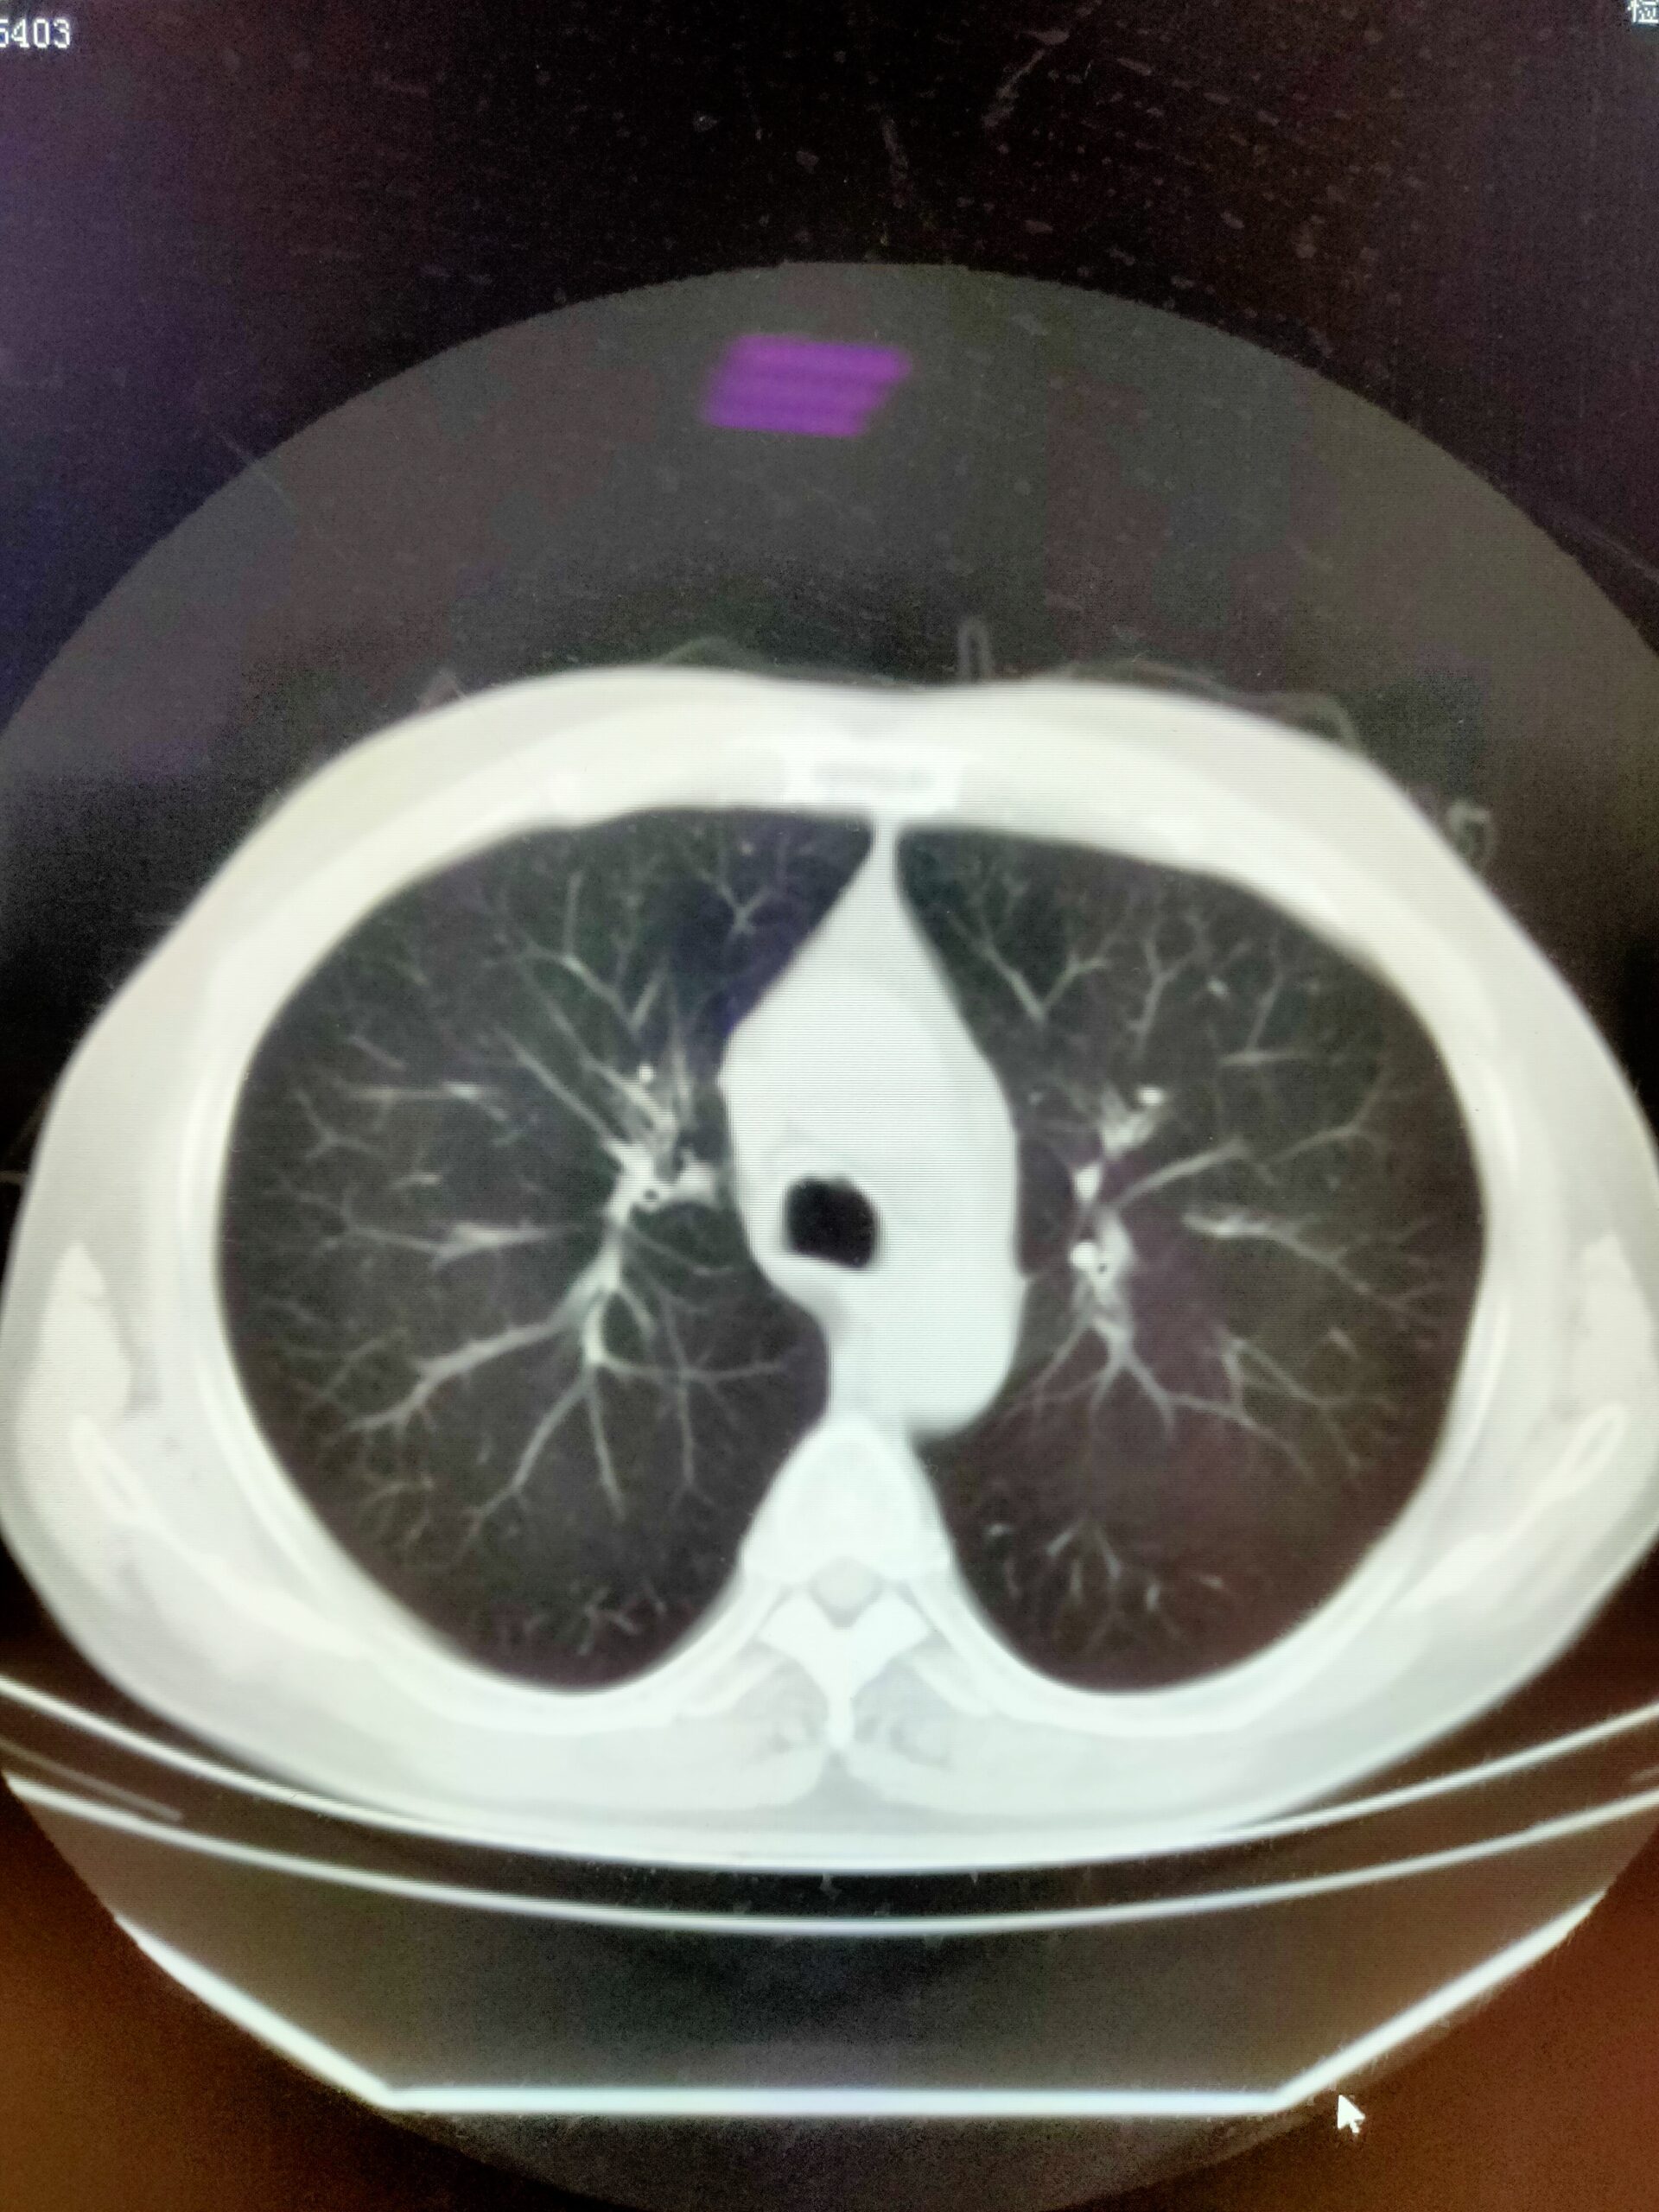

正常胸部CT